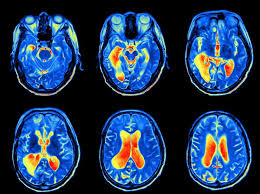

Inclusion criteria required clinical diagnosis of Parkinsons or clinically uncertain parkinsonism and. Dopamine transporter DAT-scan has high sensitivity and specificity to differentiate patients with parkinsonian syndromes Parkinsons disease multiple system atrophy and progressive supranuclear palsy from essential tremor and healthy control. International Parkinson and Movement Disorder Society evidence-based medicine review.

DaTscan is used to detect brain signs of Parkinsons disease in people with symptoms such as tremors loss of balance or coordination shuffling walk or other movement problems. DaTscan when it was approved was considered an important addition to the armamentarium of the. Truong notes that DaTscan imaging tests should be performed only by specialists who have done a high volume of Parkinsons disease scans.

The patients demographics symptoms duration clinical diagnosis and. Experience is a key factor to accurately interpreting these imaging results he explains.